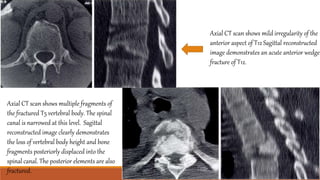

PNEUMOMEDIATINUM

Pneumomediastinum is presence of extraluminal gas within the mediastinum

Continuous diaphragm sign

Ring around artery sign

Tubular artery sign

Double bronchial sign

Ring aroundarterysign – airsurroundingthe pulmonaryartery

Tubulararterysign – airoutliningthe ascendingaorta,aorticarchand

majorbranches of aorta

Double bronchialsign – airoutlining thetracheaandproximalbronchi

Pneumopericardium– air anteriorto pericardium